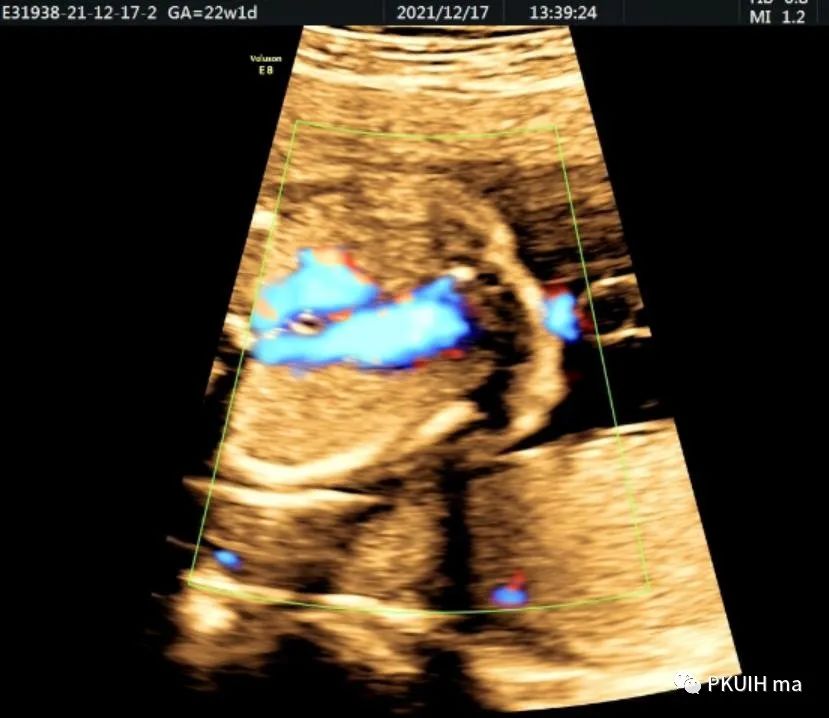

下面几张图都是右位主动脉弓、左动脉导管合并左锁骨下动脉迷走的病例,患儿出生后随访均无明显临床症状

主动脉弓走行于气管的右侧,与左位的动脉导管形成“U”型环(不完全血管环),包绕气管和食管。主动脉冠状切面可见左锁骨下动脉起自于主动脉弓降部,向左肩部走行。